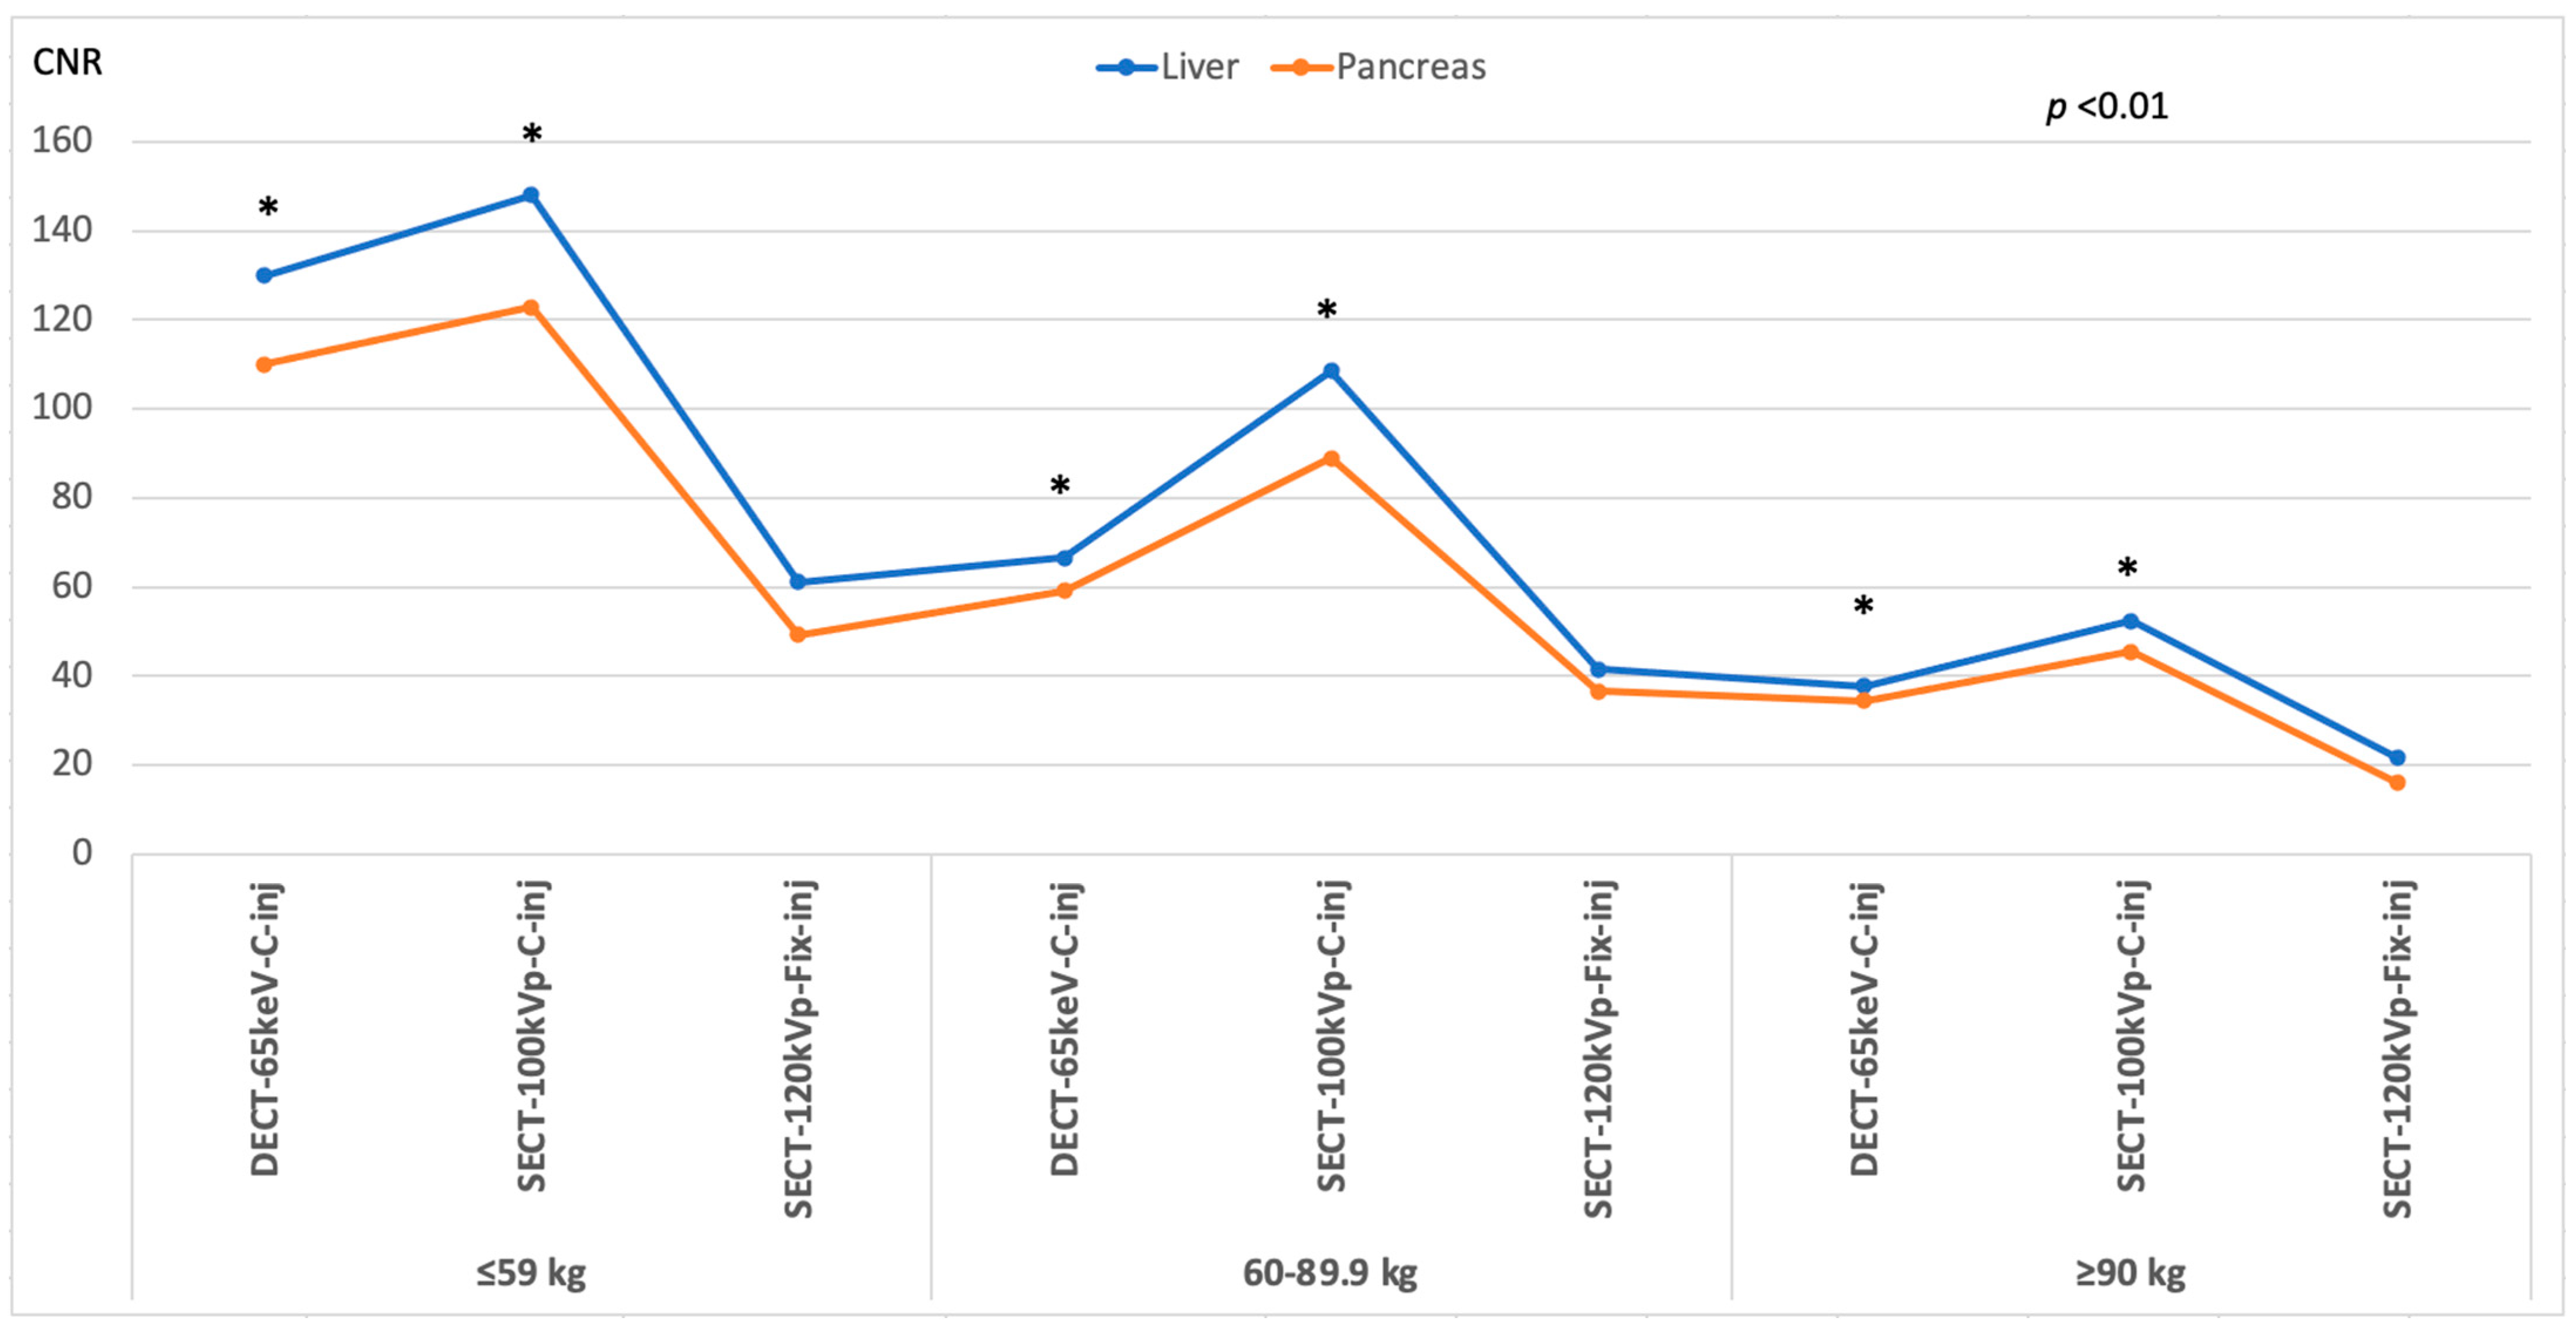

3.3. Image Quality

| Contrast-to-noise ratio | |||||||||

| Liver | 32.61 | 21.64 | <0.001 | 29.89 | 22.79 | <0.001 | 26.76 | 19.65 | 0.001 |

| ±7.03 | ±4.32 | ±6.89 | ±5.07 | ±6.01 | ±6.63 | ||||

| Pancreas | 25.83 | 18.04 | <0.001 | 24.20 | 18.43 | <0.001 | 22.22 | 16.75 | <0.001 |

| ±4.47 | ±3.97 | ±5.59 | ±3.74 | ±4.76 | ±5.48 | ||||

| Contrast-to-noise ratio | |||||||||

| Liver | 33.57 | 25.28 | <0.001 | 30.74 | 22.57 | <0.001 | 22.63 | 17.63 | 0.001 |

| ±6.30 | ±4.86 | ±7.63 | ±3.91 | ±4.73 | ±3.85 | ||||

| Pancreas | 27.11 | 20.96 | <0.001 | 22.08 | 16.47 | <0.001 | 21.70 | 16.67 | 0.001 |

| Contrast-to-noise ratio | |||||||

| Liver | 32.61 | 29.89 | 26.76 | NS | NS | NS | NS |

| ±7.03 | ±6.89 | ±6.01 | |||||

| Pancreas | 25.83 | 24.20 | 22.22 | NS | NS | NS | NS |

| Contrast-to-noise ratio | |||||||

| Liver | 33.57 | 30.74 | 22.63 | <0.001 | <0.001 | <0.001 | NS |

| ±6.30 | ±7.63 | ±4.73 | |||||

| Pancreas | 27.11 | 22.08 | 21.70 | <0.001 | 0.001 | 0.002 | NS |

| Contrast-to-noise ratio | |||||||

| Liver | 19.93 | 17.11 | 16.23 | <0.001 | <0.001 | <0.001 | NS |

| ±5.97 | ±4.45 | ±5.24 | |||||

| Pancreas | 18.40 | 16.45 | 15.94 | 0.033 | 0.076 | 0.037 | NS |